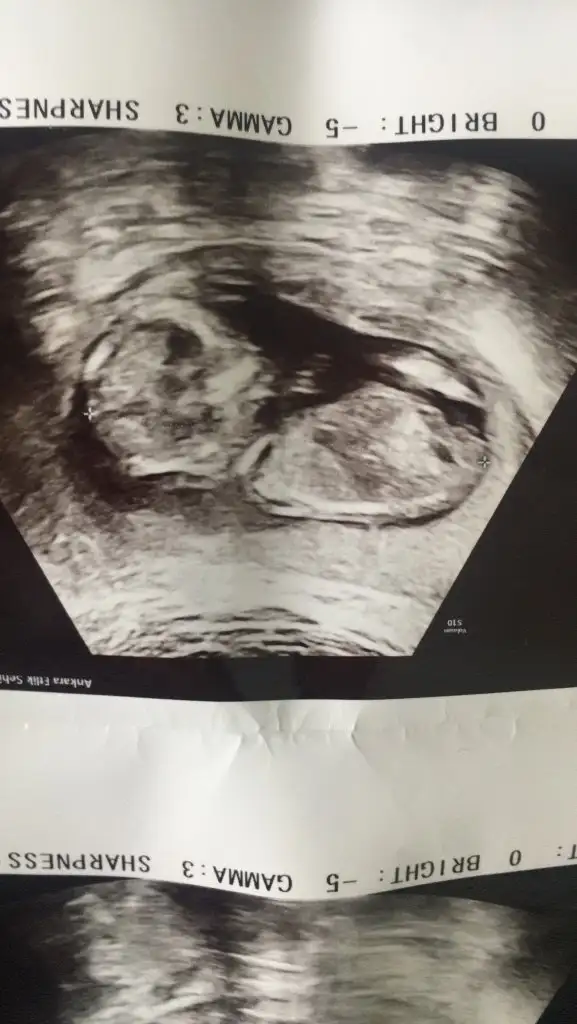

Merhaba kizlar 2 gün önce ilk kontrolume gittim devlet Hastanesi'ne doktor karından baktı kese oluşmuş içinde bebek yok dedi boş gebelik geçirdiğimive kürtaj olmami söyledi detaylı ultrasona girdiğimde bebeğimi gordum 6+2 olduğunu söyledi başka doktor sat 23 Eylül reglden 3 gün sonra tutmuş muhtemelen 4mm olduğunu soyledi fakat kalp atışı alamadik normal mi sizce genelde ,7-8. Haftalarda duyuluyormus